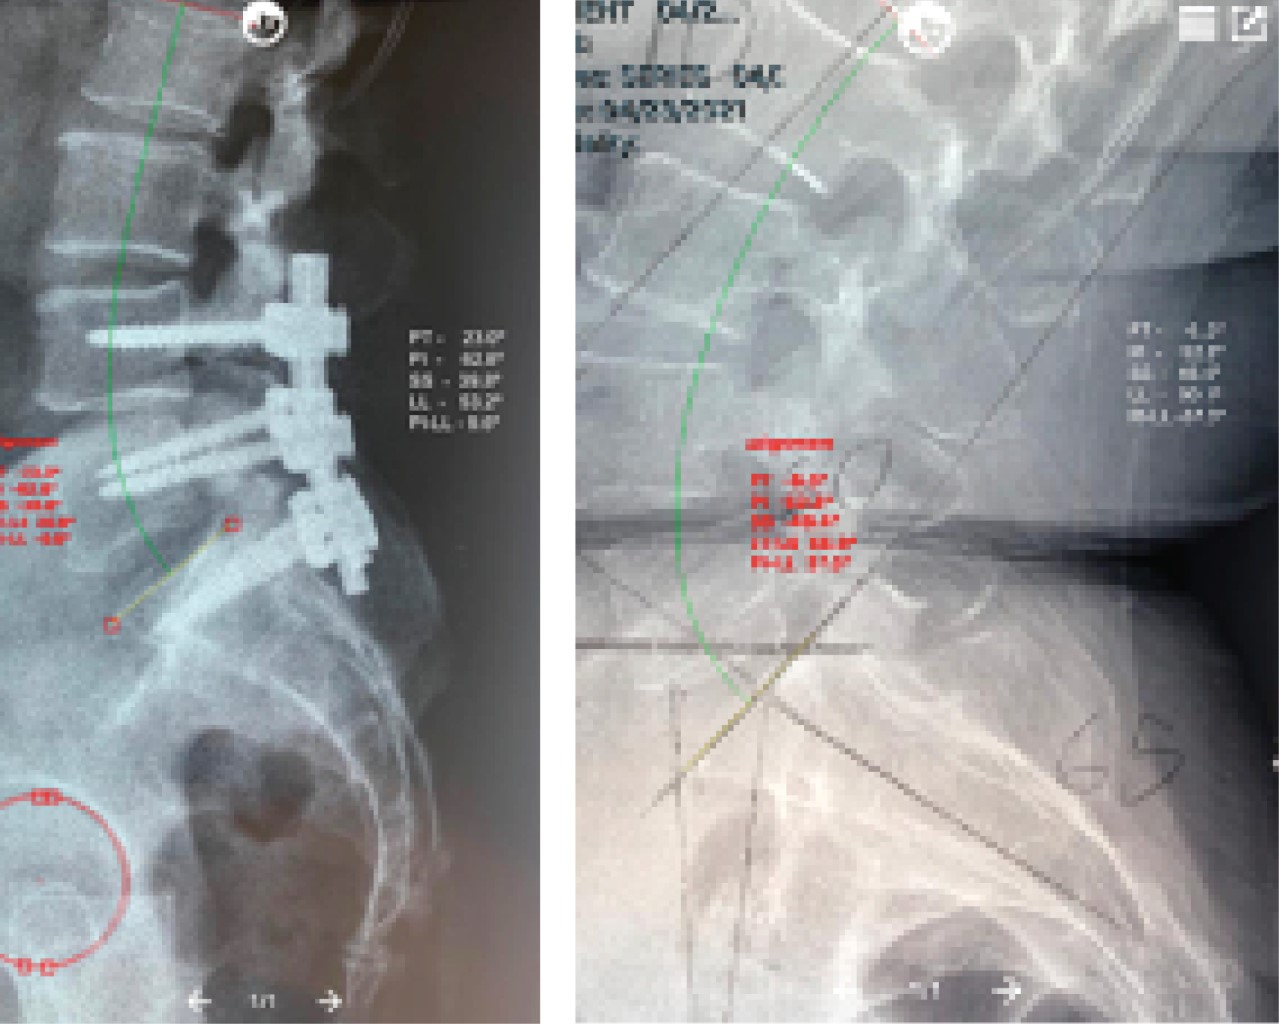

Screw to the sacrum (S1) as a treatment for the improvement of sagittal balance in patients with L4-L5 spondylolisthesis

Introduction: Spondylolisthesis is the sliding of one vertebra over another underlying one. The level that is most frequently affected (73%) is that corresponding to L4-L5. Treatments range from conservative to posterolateral fusion with fixation with transpedicular screws with intersomatic spacers. Spinopelvic balance is determined by the interaction or alignment of the pelvis and the lumbar spine being the pelvic spine imbalance an important factor in the development of this pathology. Objective: To assess the modification of the sagittal balance with the placement of a screw to the sacrum (S1) in the L4-L5 spondylolisthesis. Material and methods: Spine service patients were included, diagnosed with L4-L5 spondylolisthesis, with lumbar or lumbosacral vertebral instrumentation. A pre and postsurgical radiological study was carried out to assess the sagittal balance and the application of the Oswestry quality of life test, before and after surgery (0, 3 and 6 months). Results: 11 surgeries in patients diagnosed with L4-L5 spondylolisthesis. 27% were instrumented up to the sacrum, the rest were instrumented L4-L5, statistical analysis was performed reporting that the use of the transpedicular screw to S1 improves the sagittal balance of the lumbar lordosis, pelvic incidence, and pelvic tilt. Conclusion: The use of the pedicle screw at the level of S1 in the treatment of L4-L5 spondylolisthesis, improves the spinopelvic sagittal balance, since it acts as a fulcrum for the correction of lumbar lordosis and sacral inclination, by obtaining a good sagittal balance, obtain better clinical results.

Figure 1